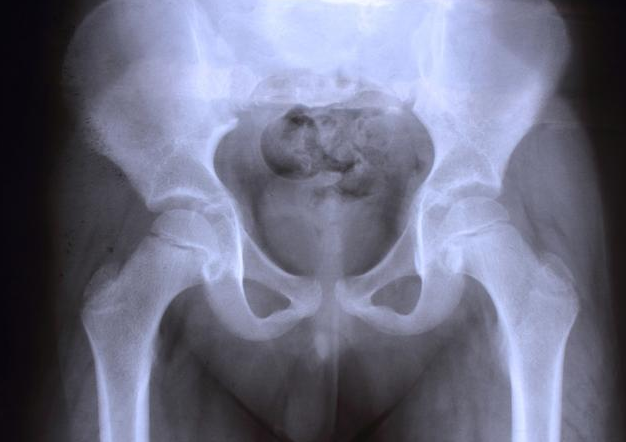

B超是檢查盆腔積液的有效手段,其實盆腔積液并不是一種疾病,而是一種表現(xiàn),生理性和病理性因素,對病理性因素要及時治療,那么,盆腔積液是怎么來的呢?接下來八寶網(wǎng)小編就來說說。

一般來說,B超檢查是發(fā)現(xiàn)盆腔積液的有效手段,女性在進(jìn)行B超檢查的時候如果發(fā)現(xiàn)盆腔臟器內(nèi)存在有液體的性質(zhì),就能夠讓醫(yī)生對滲出物作出就初步的判斷。

而盆腔積液有分生理性和病理性,如果在進(jìn)行B超檢查的時候盆腔內(nèi)的大量積液滲出比較差,就說明是一些婦科炎癥導(dǎo)致盆腔積液的發(fā)生,這事屬于病理性的,需要及時進(jìn)行治療。

生理性盆腔積液和病理性盆腔積液兩種,生理性盆腔積液屬于正常現(xiàn)象,而病理性盆腔積液可發(fā)生在盆腔炎、附件炎或子宮內(nèi)膜異位癥之后。